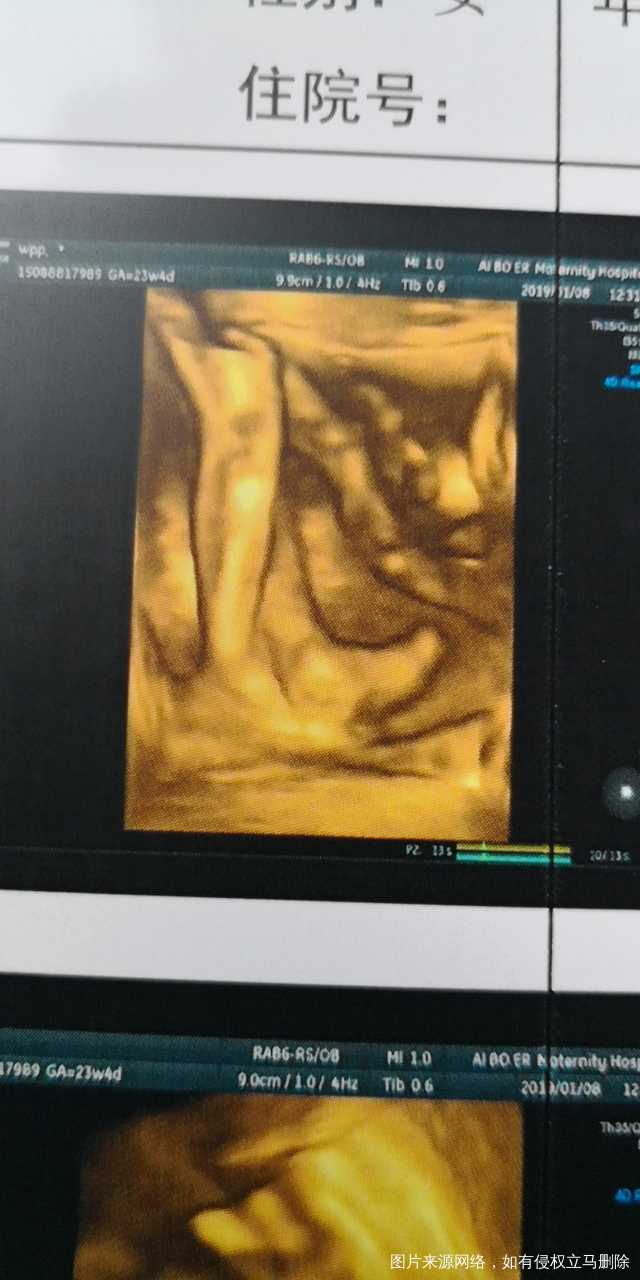

四维彩超顺利通过,愿明天糖水也顺顺利利通过